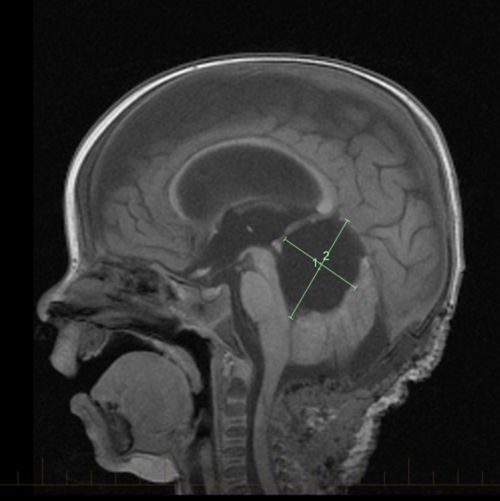

6 originally described in the 1980s, atrt has been. Morning headache or headache that goes away after vomiting. Mri of an atypical teratoid rhabdoid tumor (atrt) in the brain. The other symptoms depend on where in the body the cancer. The most common symptoms include: An atypical teratoid rhabdoid tumor, is a fairly rare aggressive tumor usually diagnosed in young children that forms in the tissues of the central nervous system. A neuropathologist should then review the tumor tissue. Headache, which is often worse in the morning or improves after vomiting Since many of the tumors occur in the posterior fossa, they present like other posterior fossa tumors, often with headache, vomiting, lethargy, and ataxia (unsteady gait). Atypical teratoid rhabdoid tumor (atrt) of the central nervous system (cns) is a highly malignant embryonal neoplasm (grade 4 according to the world health organization classification) that typically occurs in children aged <3 years. Anyone can get cancer — even babies. Check with your child's doctor if your child has any of the following: Cancers in children are sometimes hard to recognize because common illnesses or everyday bumps and bruises can mask the early warning signs.

What Is Atypical Teratoid Rhabdoid Tumor At Rt from www.stbaldricks.org Like a lottery nobody wants to win, we suddenly found ourselves in a category of cancer so small, so. Symptoms may occur when a tumor presses on a nerve or damages certain parts of the brain. They are found in fewer than 3% of children with brain tumors and are most often seen in children three years of age or younger. Since many of the tumors occur in the posterior fossa, they present like other posterior fossa tumors, often with headache, vomiting, lethargy, and ataxia (unsteady gait). Mri of an atypical teratoid rhabdoid tumor (atrt) in the brain. To get an accurate diagnosis, a piece of tumor tissue will be removed during surgery, if possible. Atrt is a very difficult tumor to cure, and, unfortunately, the outcomes remain poor. These tumors grow quickly, and symptoms may worsen in a very short time.

Because atypical teratoid/rhabdoid tumor is fast growing, signs and symptoms may develop quickly and get worse over a period of days or weeks. Little is known, however, about the symptoms and suffering at the end of life in children with cancer. Lori with her son, issy, while he was in treatment for a brain tumor. Signs and symptoms may be caused by atrt or by other conditions. Some other symptoms of cancer in children might include fever, frequent infections, bone pain, night sweats, vomiting, and headaches, all of which children often have when they have more common and less serious viral infections or other common problems of childhood. Headache, generally upon awakening in the morning hydrocephalus, where there is a buildup of fluid in the brain, can increase head size in infants or headaches and vomiting in older children nausea and vomiting, often worse in the morning and improve throughout the day Malignant rhabdoid tumors occur most commonly in infants and toddlers; They may also occur when the brain swells or there is fluid buildup in the skull. Cancers in children are sometimes hard to recognize because common illnesses or everyday bumps and bruises can mask the early warning signs. In general, older children with atrt tend to do better than younger children. Atypical teratoid/rhabdoid tumor (atrt) is a malignant embryonal tumor of the cns that is composed of rhabdoid cells, with or without fields resembling classical primitive neuroectodermal tumor. Atrt symptoms vary widely depending on the patient's age and the tumor's location. Mri of an atypical teratoid rhabdoid tumor (atrt) in the brain.